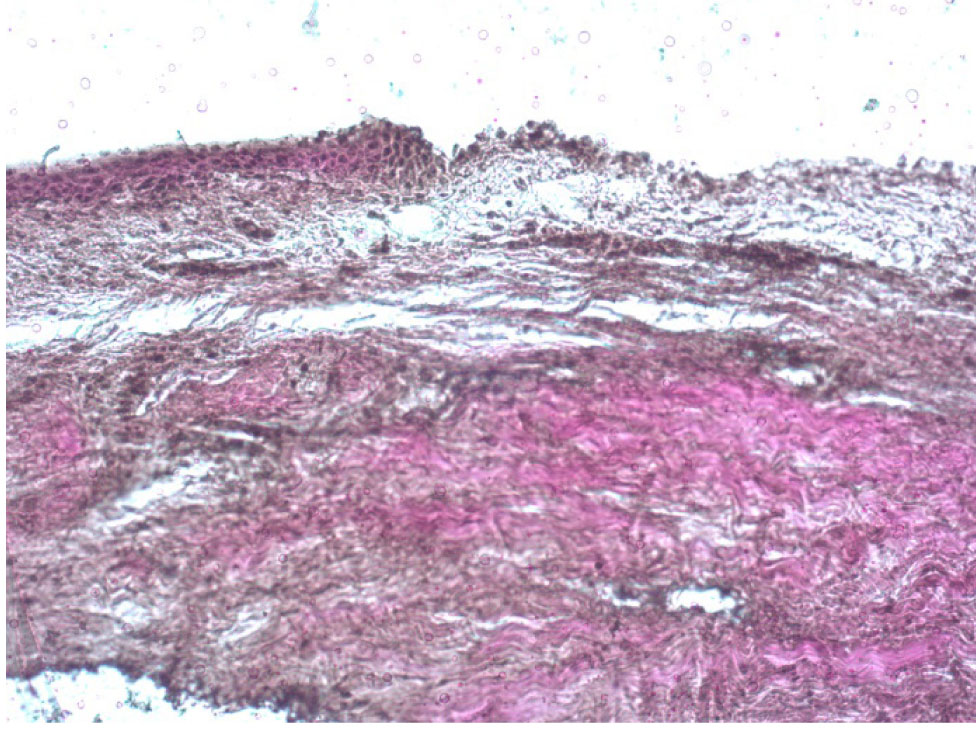

Во второй группе, где проводилась ограниченная по диаметру эксимерлазерная деэпителизация на глубину ⅔ эпителиального слоя с последующим механическим удалением оставшейся ⅓ эпителия, визуализировались как деэпителизированные участки, так и зоны с сохраненным эпителием, где определялась слоистость его строения от рядов кубических до плоских клеток без элементов ороговения (рис. 6). При окраске по Ван Гизону видно, что такие участки деэпителизации дали возможность пройти раствору рибофлавина в строму роговицы на всю ее глубину, что отразилось в появлении лакунарных пространств на всей площади поперечного среза роговицы до десцеметовой мембраны. Коллагеновые волокна при этом сохранили однонаправленность ориентации параллельно поверхности роговицы.

Рис. 6. Роговица свиного кадаверного глаза после проведения частичной эксимерлазерной деэпителизации, окраска по Ван Гизону, об. ×10

Наибольшее разрыхление передней стромы роговицы отмечалось в проекции зоны деэпителизации. Однако аналогичная картина с появлением большого количества лакунарных пространств между волокнами коллагена наблюдалась и под сохраненным эпителием, что говорит о наличии межламеллярного распространения раствора рибофлавина на область, превышающую по размерам зону деэпителизации, что подтверждает целесообразность проведения деэпителизации только в зоне кератоконуса и осуществления ультафиолетового облучения как в зоне полной деэпителизации, так и перифокально с захватом роговицы с сохранным эпителием.